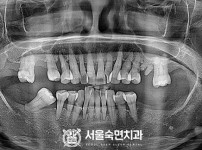

임플란트-전후사진3

임플란트-전후사진4